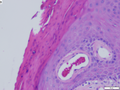

Herpes Zoster

Changes of herpes zoster in lower right abdominal skin of a 48 yo Hispanic man. A. Note the edema at the dermoepidermal junction along with a focal separation at the left as well as the inflamed superficial and deep blood vessels. B,C. Careful examination along the junction uncovers smudged chromatin diagnostic of viral infection. D. Vasculitis associated changes include extravasated neutrophils with nuclear dust, as well as pervascular macrophages, lymphocytes and occasional eosinophils.